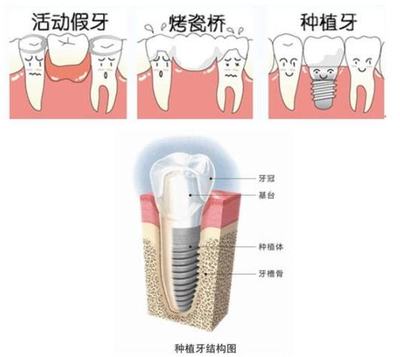

烤瓷牙是现在流行的一种牙齿,可以让你的黄牙洁白如雪。这也赢得了很多朋友的喜爱。毕竟,洁白的牙齿不是让每个人都幸运的。烤瓷牙可以有效帮助牙齿看起来更健康。那么烤瓷牙需要注意什么呢?接下来我会详细告诉你什么是烤瓷牙,烤瓷牙有什么危害,烤瓷牙有什么不适。什么是烤瓷牙?烤瓷牙是固定义齿的一种,内层是金属。

颜色非常接近人类牙齿的本来颜色。患者不能自行摘下,而是用水泥粘在磨好的牙齿上。瓷层颜色可根据患者邻牙颜色进行搭配,修复后美学效果一般较好。烤瓷牙口腔异味的危害由于烤瓷牙与真牙之间密封不彻底,食物残渣容易残留在牙齿内,牙齿内细菌代谢产生异味,容易形成口臭。受不了忽冷忽热* * *在医生配牙的过程中,牙医不小心磨坏了牙齿。

首先,如果选择一个靠谱的机构来做,危害是很小的。一般伤害都是为了便宜而选择不靠谱的烤瓷牙材料和技术不到位的医生造成的后续伤害。一、口腔不健康,易感染:不是每个人都适合做烤瓷牙。如果口腔环境不好(如牙周炎、牙龈出血、牙龈肿胀等。),很容易造成感染。另外,牙齿和牙冠密封不好,容易引起继发牙病。二、连体烤瓷牙容易引起继发牙病:一是连体烤瓷牙咀嚼时受力不均,更容易松动,给细菌可乘之机;二是制作烤瓷牙时,医生对牙齿的磨损过大,导致烤瓷牙冠离牙髓太近,容易诱发感染。